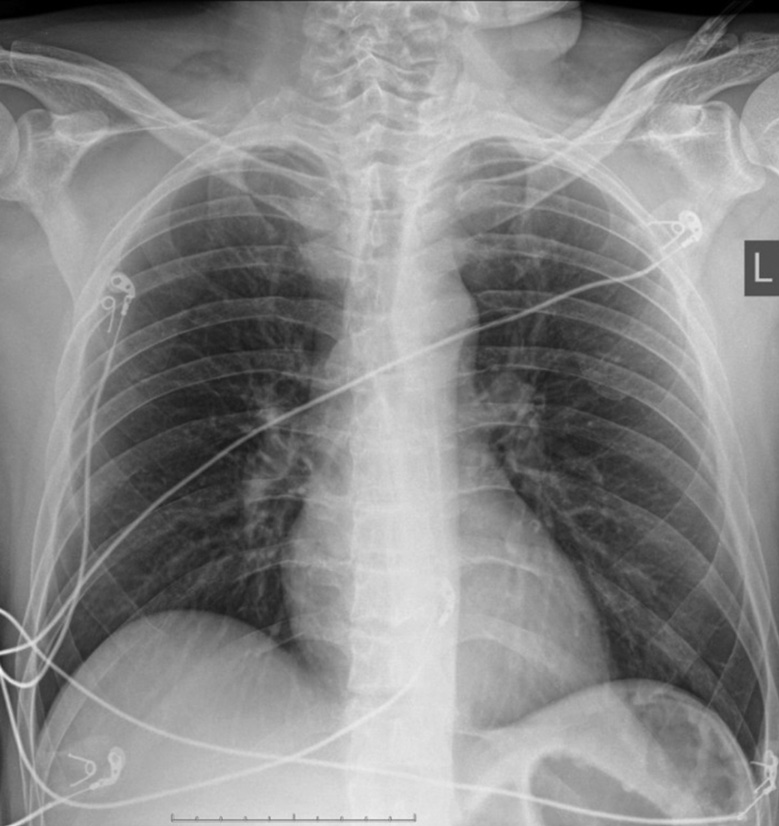

Рис. 1. Рентгенограммы органов грудной клетки в прямой проекции пациента А (57 лет, рассчитанная начальная концентрация карбоксигемоглобина в крови 56%, тяжелая степень интоксикации), выполненные на 1-е (а) и 9-е (b) сутки после поступления.

Fig. 1. X-rays of the chest organs in the direct projection of patient A (57 years old, the calculated initial concentration of carboxyhemoglobin in the blood is 56%, corresponds to a severe degree of intoxication), performed on days 1 (а) and 9 (b) after admission.

Длительность госпитализации пациентов с интоксикацией тяжелой степени составила 4 [4; 6] сут, средней степени — 4 [2; 5, 7] сут, легкой степени — 3 [2; 5, 5] сут. Значимых различий по длительности госпитализации пациентов в зависимости от степени тяжести состояния, определенного по рассчитанной начальной концентрации карбоксигемоглобина в крови, выявлено не было. Доля пациентов, у которых выявили интерстициальные изменения в легких, значимо не зависела от степени тяжести состояния (табл. 1). Так, у пациентов с тяжелой (рис. 1) и легкой (рис. 2) степенью состояния определены сходные интерстициальные изменения в тканях легких на рентгенограммах органов грудной клетки. В то же время у 37 ± 15% пациентов в тяжелом состоянии интерстициальных изменений в тканях легких при анализе рентгенограмм органов грудной клетки выявлено не было (рис. 3).

У 47 ± 7% пациентов были выявлены интерстициальные изменения в тканях легких: усиление легочного рисунка за счет сосудистого компонента, очаги консолидации легочной ткани. При анализе рентгенограмм таких пациентов в динамике отметили нормализацию легочного рисунка и регресс очагов консолидации (рис. 1, 2). Длительность госпитализации пациентов с выявленными изменениями на рентгенограммах составила 5 [4; 8] сут, без интерстициальных изменений (53 ± 7%) — 3 [2; 5] сут.